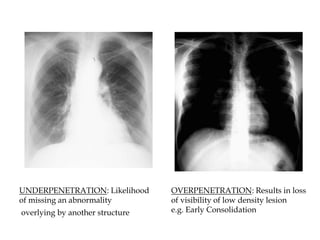

b. Penetration

 On a good PA film, the

thoracic spine disc spaces

should be barely visible

through the heart but bony

details of the spine are not

usually seen.

 On the other hand

penetration is sufficient that

bronchovascular structures

can usually be seen through

the heart.

UNDERPENETRATION: Likelihood

of missing an abnormality

overlying by another structure

OVERPENETRATION: Results in loss

of visibility of low density lesion

e.g. Early Consolidation

UNDERPENETRATION: Likelihood of missingan abnormality overlying by another structure OVERPENETRATION: Results in loss of visibility of low density lesion e.g. Early Consolidation